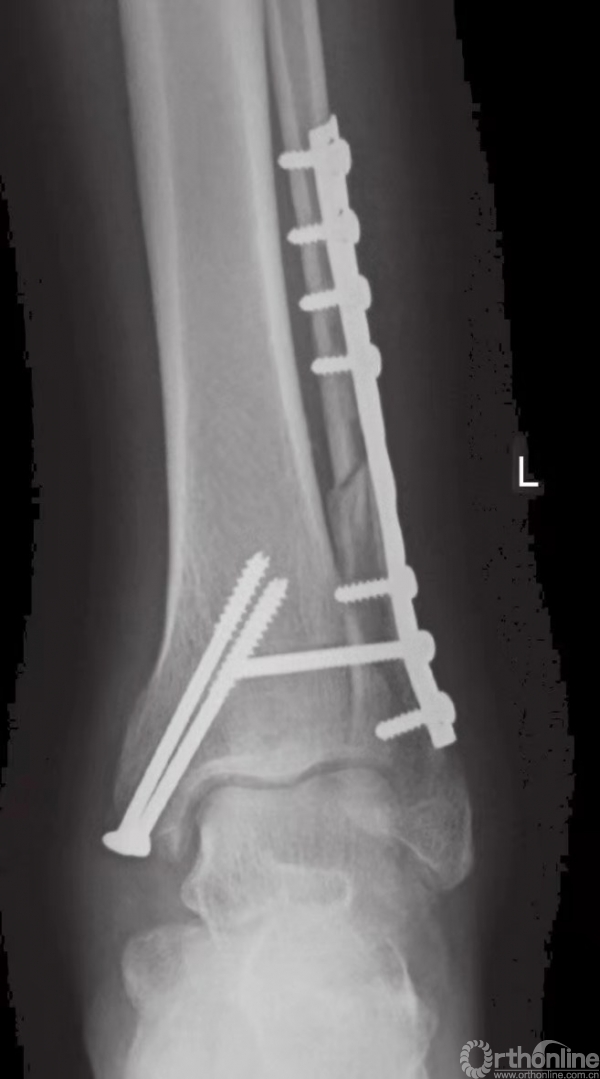

如果下胫腓联合不稳,则须进行固定,固定时采用皮质骨螺钉。由于腓骨在解剖关系上位于胫骨的后外侧,因此应将螺钉从后向前以30°的角度嵌入。一般认为,三皮质骨螺钉固定足以保证下胫腓联合的稳定性。螺钉应至少高过关节线2cm(图24和图25)。

图24 下胫腓骨螺钉置入方法

图25 通过钢板的皮质骨螺钉固定旋前外旋型下胫腓联合损伤